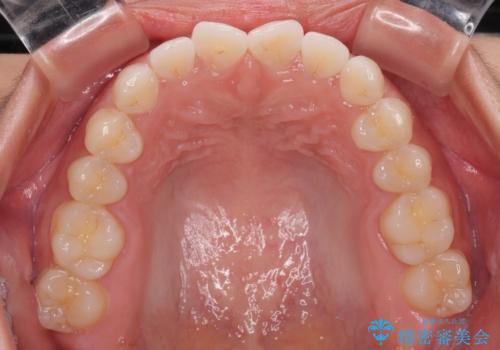

- 上下前歯のデコボコを気にして来院された患者様です。

ワイヤー矯正でもマウスピース矯正でも可能でしたが、短期間で、自身の手を煩わせることなく治療を行いたいとのことで、ワイヤー装置にて矯正治療を行うこととしました。

僅か半年強、あっという間に治療を終えることができました。